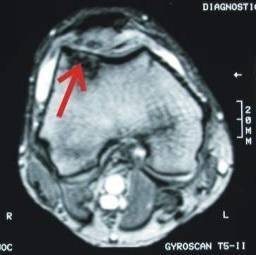

Severe cartilage damage to the patella in an MRI representation